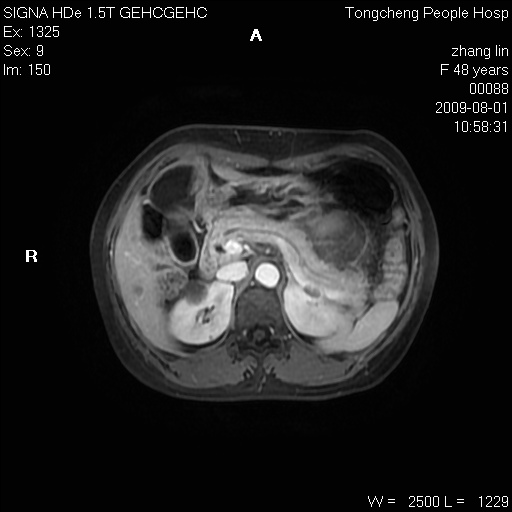

女,48岁。健康体检,彩超发现右肾占位性病变。平素健康。

临床诊断:右肾占位性病变,性质待定(囊肿?肿瘤?)。

上中腹部mr平扫+增强扫描,图像如下:

右肾上极见一类圆形病灶,t1wi呈等信号t2wi呈等高混杂信号,三期增强无强化,边界清---考虑囊肿出血。

同反相位均表现为等信号,病变无强化,考虑含蛋白的囊肿可能,弥散加权相或许有些帮助,

肝囊肿

慢性胆囊炎